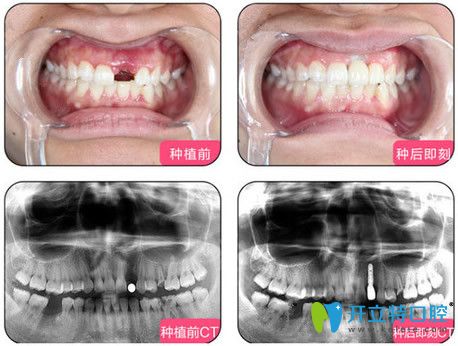

一、單顆種植牙案例:

單顆種植技術(shù):適用于單顆不相鄰的牙齒缺失,年輕人牙齒意外掉落的修復(fù)。

烏魯木齊凱樂(lè)口腔單顆種植牙效果圖